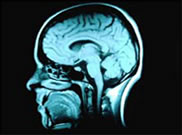

Brain Injury Case Management

Brain injury case management can mean having to deal with some complex issues. This is why it is advisable to always choose a case management team that has experience with this type of injury. Rehabilitation from a catastrophic brain injury can take a lot of work and involve dealing with a large number of different professionals and services means that any case manager will really need to be up to speed. The good news is that utilising brain injury case management can make a huge difference by ensuring that things move faster and more effectively. More and more clients and their families are becoming convinced of the need for this type of service – chances are that if you try it you will be convinced too.

A brain injury is one of the most difficult injuries to recover from- a large number of people will never be able to fully return to how things were before their accident. For some people the brain injury might leave a lasting physical disability while for others it could mean a permanent change to their personality. Rehabilitation can make a huge difference though and this is why you want to be sure that you are getting the best possible assistance Here are just some of the ways that brain injury case management can help during the rehabilitation process.